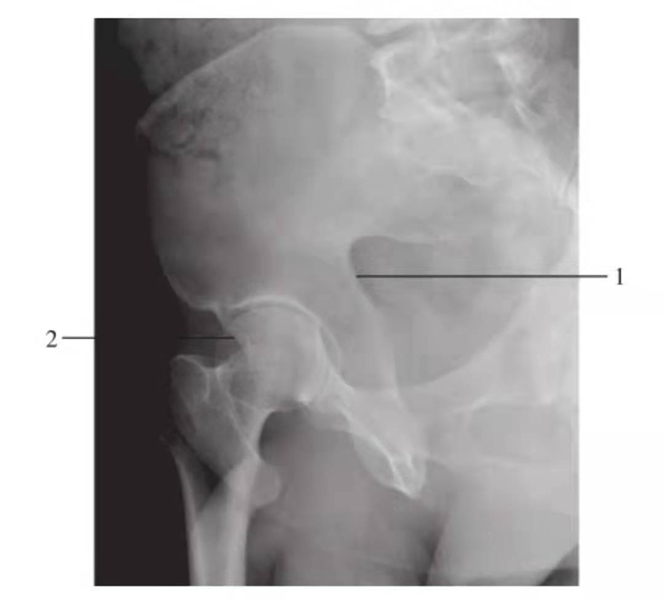

髂骨斜位

图10 右侧髂骨斜位

1.后柱;2.髋臼前唇